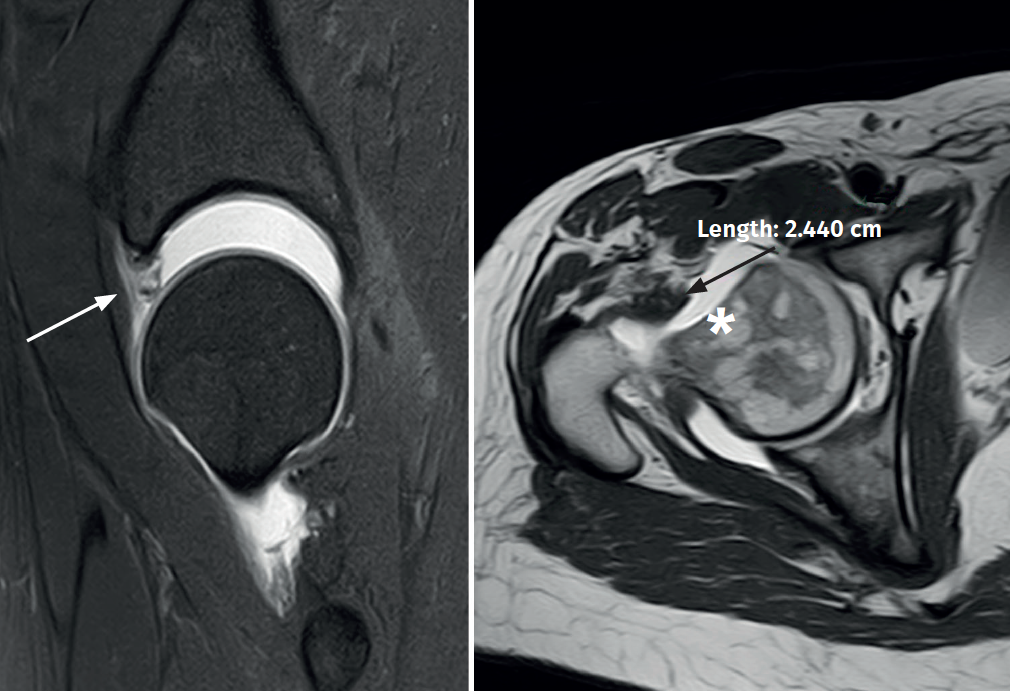

A 38-year-old woman subjected to surgery three years ago due to right femoroacetabular impingement presented with residual pain. At exploration, the Faber and impingement maneuvers were very positive, as was the dial test. Anterior instability maneuvering (abduction and extension) with apprehension during gentle external rotation maneuvers also proved positive. No rotational anomalies were evidenced at exploration. The modified Harris score was 68 points. Radiographically, the head-neck junction was correct, in the same way as acetabular coverage. On the other hand, joint magnetic resonance imaging showed areas of 11-3 o'clock acetabular chondrolabral degeneration / re-rupture and a deficient joint capsule corresponding to type 3 of the Aoki classification(5) (Figure 1), with no version structural alterations of the acetabulum and femur. In addition, important joint distraction displacement with gentle traction was observed. Postsurgical hip microinstability due to mixed capsular and labral joint sealing loss was diagnosed. In view of these findings, simultaneous arthroscopic labral and capsular reconstruction was proposed.

Figure 1. Right hip: joint magnetic resonance imaging view showing labral deficiency and re-ruptures (arrow), and an important capsular defect (star) with marked joint displacement upon traction.